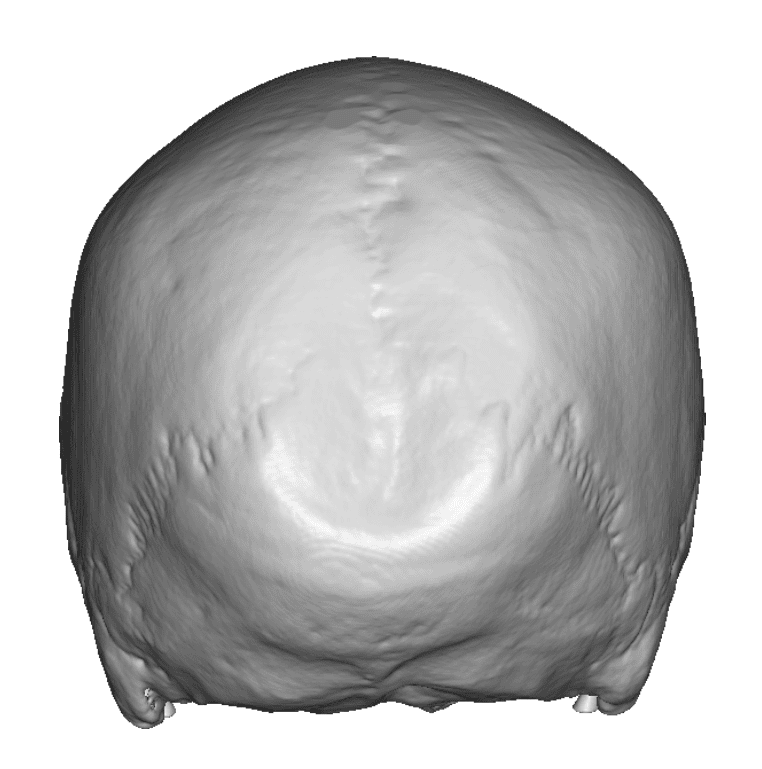

Desire for removal of occipital knob on back of skull.

Occipital knob skull reduction done through a small 3cm overlying skin incision.